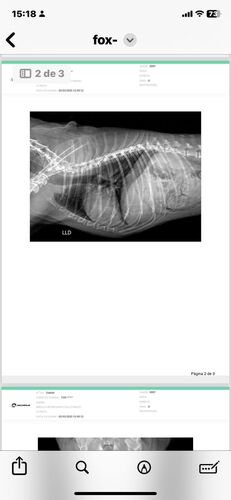

No dia 02 de março de 2025, Fox sofreu um grave acidente. Uma linha de pipa com cerol passou pela laje de casa e cortou a Fox. Assustada, ela caiu da laje de uma altura de 3 metros, sofrendo diversas fraturas nas patinhas e costelas, lesões internas que prejudicaram sua mobilidade.